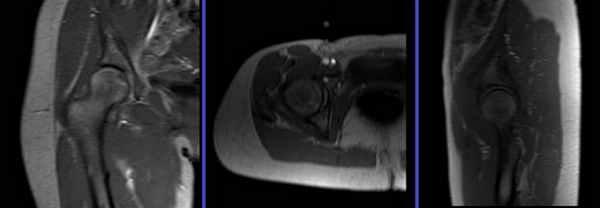

3. МРТ при дисплазии тазобедренного сустава:

• Выявляются морфологические изменения, сходные с таковыми при рентгенографии

• Лимб суставной губы: увеличение верхней суставной губы, позволяющее частично компенсировать недостаток костной ткани:

о Как правило, отмечаются признаки мукоидной дегенерации

о Часто возникают комплексные разрывы

(Справа) МР-артрография в режиме Т2ВИ FSE FS, коронарный срез, пациент 25 лет: наблюдается неглубокая вертлужная впадина. Видны разрыв суставной губы, пара-лаоральная киста и обширные дегенеративные изменения лимба суставной губы.